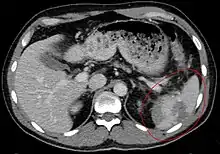

Splenic rupture is usually evaluated by FAST ultrasound of the abdomen.[4] Generally this is not specific to splenic injury; however, it is useful to determine the presence of free floating blood in the peritoneum.[4] A diagnostic peritoneal lavage, while not ideal, may be used to evaluate the presence of internal bleeding a person who is hemodynamically unstable.[5] The FAST exam typically serves to evaluate the need to perform a CT scan.[5] Computed tomography with IV contrast is the preferred imaging study as it can provide high quality images of the full peritoneal cavity.[4]